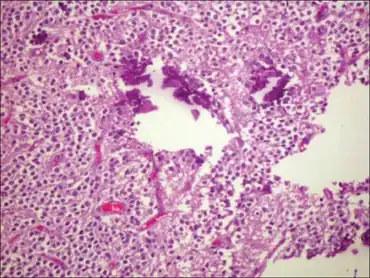

Neurocytoma is a type of nervous system benign tumor which is primarily derived from nervous tissue.[1]